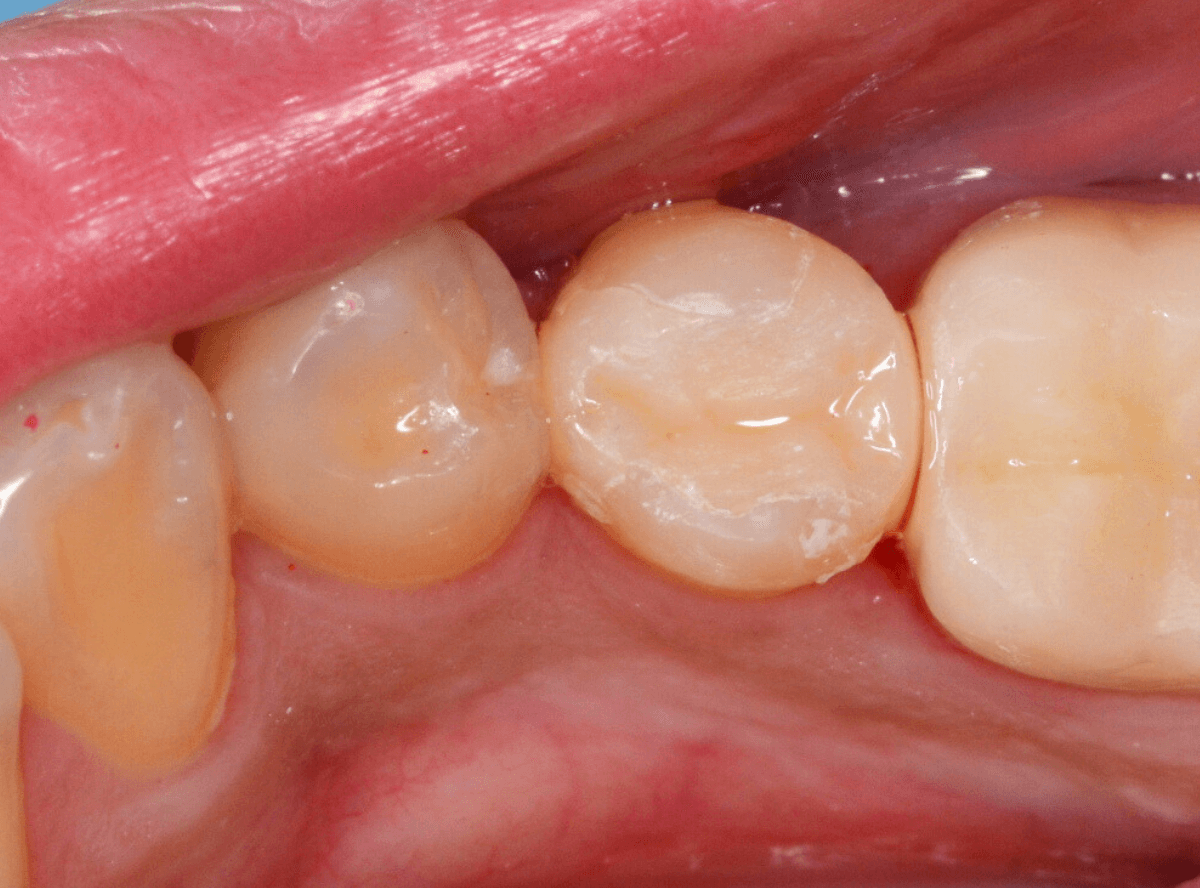

治療後の状態です。

自然な仕上がりで、患者さんにもご満足いただけました。